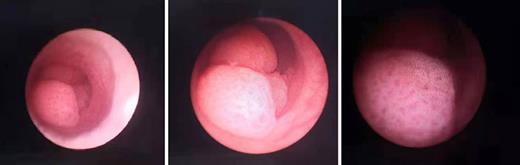

A forty-four-year-old man has come to our hospital due to hematuria for 1 week, and ultrasound showed that there were multiple calculi in the left kidney. A few days later, ureteroscopy with holmium laser lithotripsy was performed. However, during the surgery, three cauliflower-like neoplasms were found in the left proximal ureter (shown in Fig. 1). Apart from lithotripsy, we have checked that there was no neoplasm in all left renal calices through flexible ureteroscope. Besides, biopsies of the neoplasms were also taken from the ureter, and later results have shown that they were high-grade papillary urothelial carcinomas. Moreover, after the surgery, renal emission computed tomography has suggested that the patient may also suffer from CKD, while the injury of the right kidney was more severe than that of the left one. Besides, we got to know that he has taken Aristolochia for medical use without the permission of doctors, which may result in ureteral carcinoma. Because of his renal function, the patient asked for kidney-sparing therapy regardless of high-risk pathological finding. Later, segmental ureterectomy of the left side was conducted, and pathological finding of the carcinoma was the same as the first time.

Three cauliflower-like neoplasms were found in the left proximal ureter.